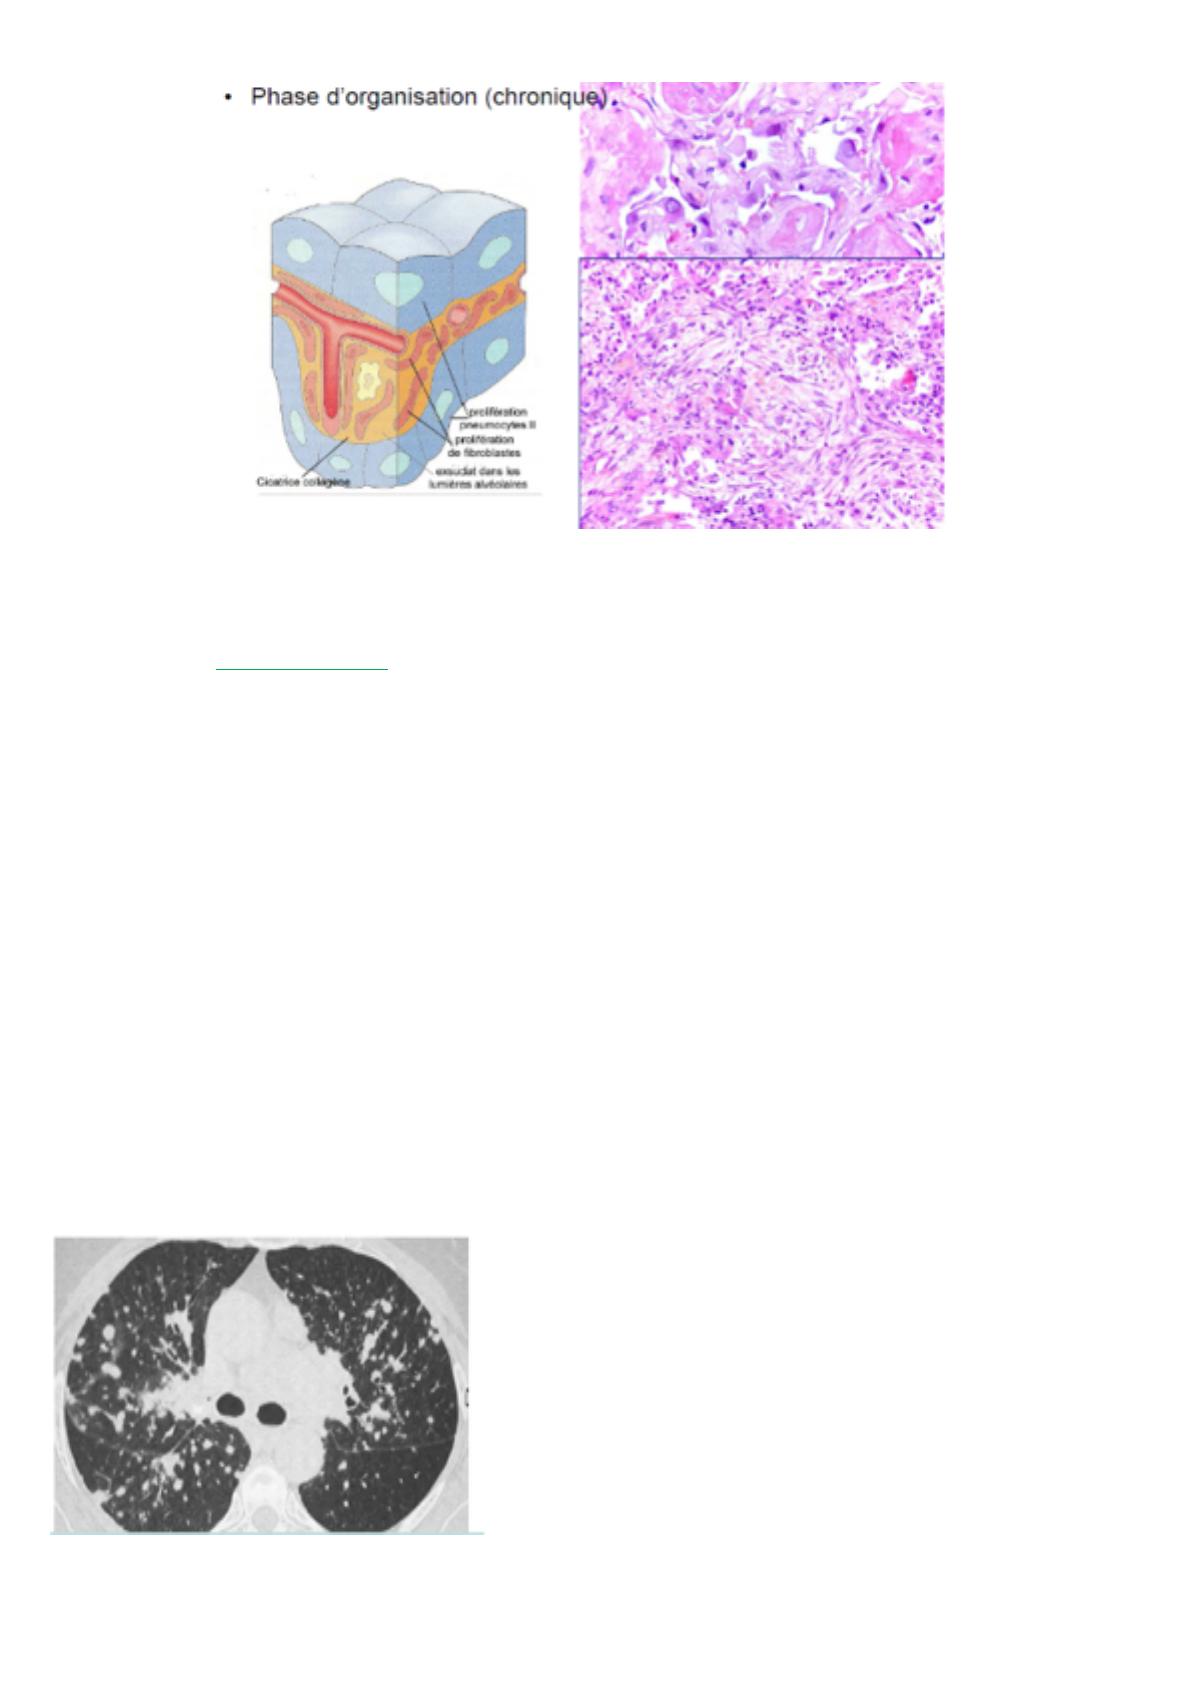

B. Phase chronique

A ce stade, soit ça passe

soit ça casse. Si le patient

passe cette phase aigüe,

il va y avoir une phase

chronique qui va consister

en une fibrose avec des

bougeons cicatriciels

avec des fibroblastes

fusiformes, comme une

cicatrice cutanée. Les pneumocytes vont être hyperplasiques (plus gros).